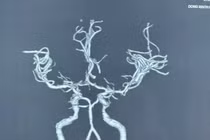

Cấp cứu ngừng tuần hoàn (ngưng tim, ngưng thở) là một cấp cứu rất khó khăn, đòi hỏi sự liên tục, khẩn trương và chính xác, bởi chỉ cần ngưng tim, ngưng thở 4 phút đã để lại di chứng, tổn thương khó hồi phục, thậm chí tử vong.